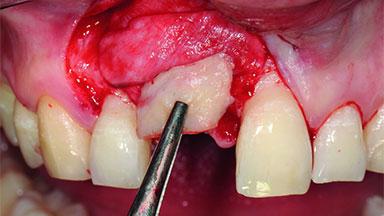

Replacement of a Compromised Upper Right Central Incisor: Hard- and Soft-tissue Augmentation, Late Placement of an RC Bone Level Implant

Bone Augmentation Horizontal|Simultaneous|Staged

Augmentation Materials Xenogenous|Membrane

Soft Tissue Grafting Simultaneous